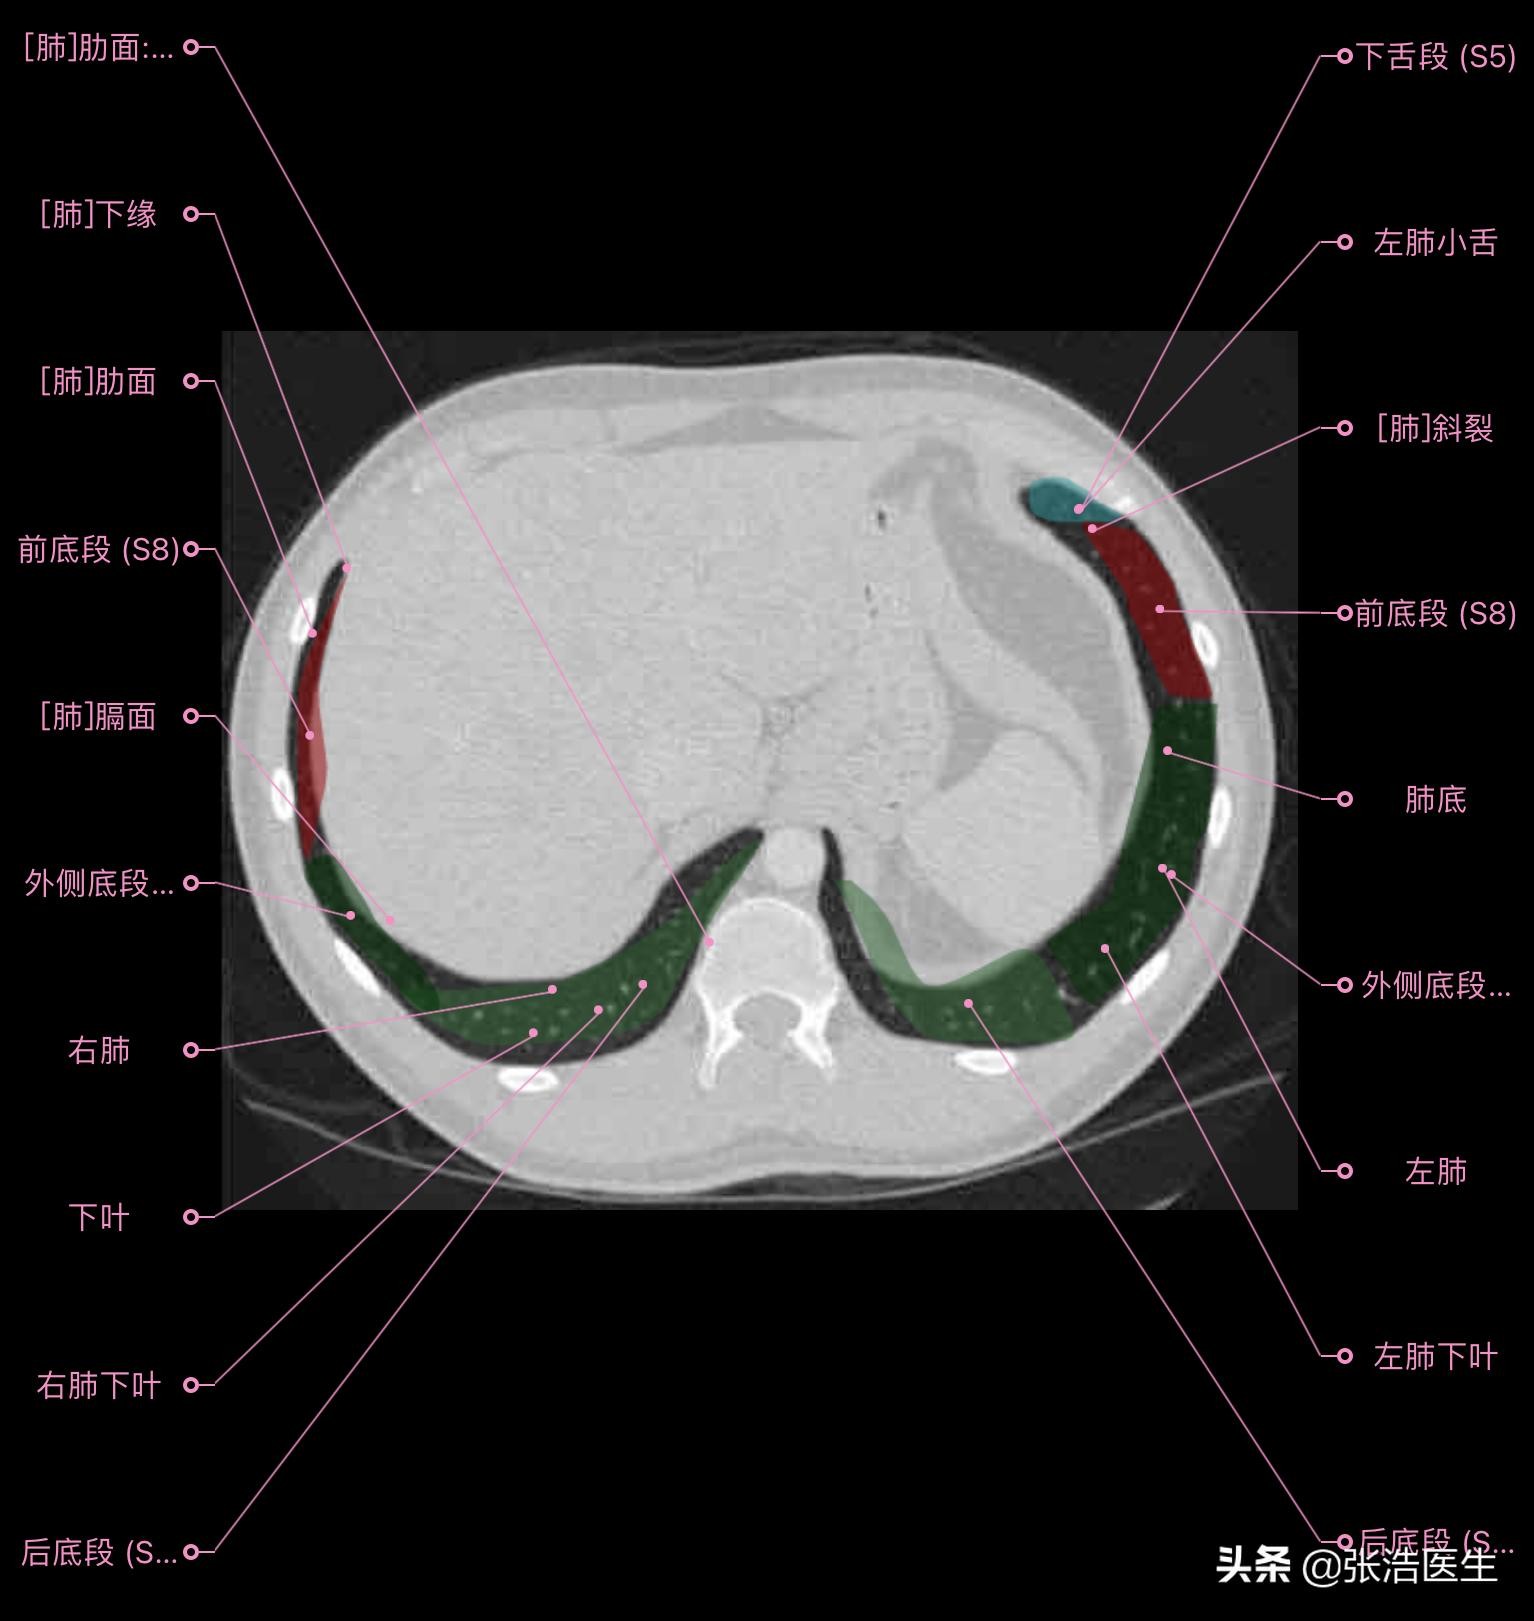

肺部CT横断面 高清解剖图谱

精选15层常用解剖断面

每一层都带有详细标注,值得收藏学习!

肺部CT横断面高清解剖图谱(图层9)